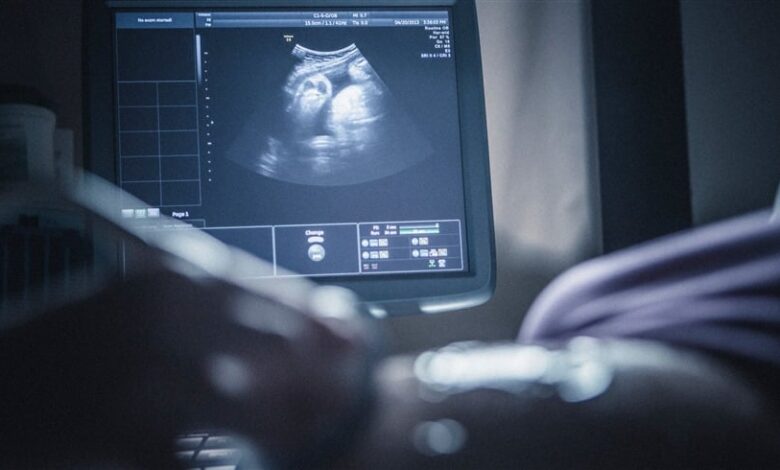

في حادثة طبية استثنائية أثارت دهشة الأطباء، اكتشفت سيدة مصرية خلال فحص روتيني أنها تحمل في رحمها تسعة أجنة دفعة واحدة، في واحدة من أندر الحالات المسجلة في الطب الحديث.

ووفق وسائل إعلام محلية، لم يكن الزوجان يتوقعان أكثر من سماع نبض جنين واحد، لكن لحظة الاطمئنان على الجنين بداخل رحم الأم تحولت إلى صدمة حقيقية عندما أظهر جهاز السونار وجود تسعة أكياس حمل داخل الرحم.